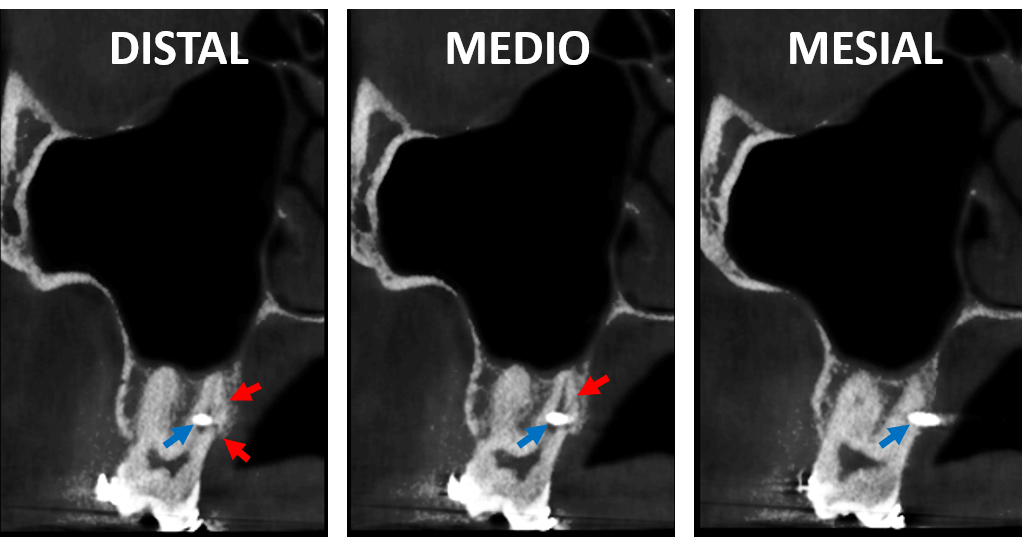

En cortes axiales (Fig.3) se observa la perforación de la raíz palatina del órgano dentario 17 por el dispositivo de osteosíntesis en estrecha proximidad con la superficie furcal (flecha azul). Nótese los trazos de fractura (flechas rojas) en proximidad con la tabla ósea palatina.